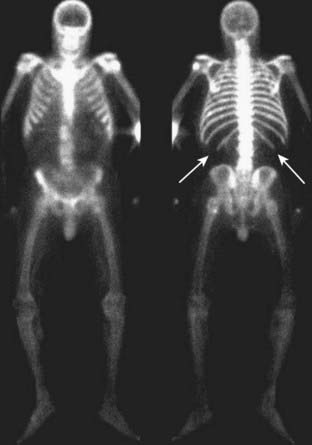

image With diffuse bone metastases, a so-called superscan may be seen on radionuclide bone scan. The superscan demonstrates high radiotracer uptake throughout the skeleton, with poor or absent renal excretion of the radiotracer (Fig. 21-4).

image

Figure 21-4 Radionuclide bone superscan.

Anterior and posterior views of the axial and appendicular skeleton show the increased distribution of bone radiotracer uptake throughout the skeleton. This is the picture of the so-called superscan produced by osteoblastic metastatic disease involving every bone leading to high uptake throughout the skeleton, with poor or absent renal excretion of the radiotracer (solid white arrows point to the absence of excretion by the kidneys).